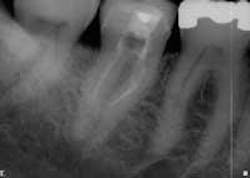

This is rarely satisfactory to the patient and/or doctor and not a profitable method of practice. We all know, or should know, our degree of skill, equipment, and comfort level. As clinicians, few of us can be all things to all people. If we know of a clinician who is more skilled in a given endodontic area, we are duty-bound to act in the best interest of the patient and refer. As a practicing endodontist, I refer a limited number of patients for IV sedation, as required. The patients who get the best possible treatment, even if referred elsewhere, can become our greatest advocates because they know we have their best interest at heart. The converse is true. The “I’ll try anything” mentality can bring forth iatrogenic events that rarely leave the tooth with the same integrity that it would otherwise have. Work that has to be re-treated is never profitable (see Figs. 1 and 2).